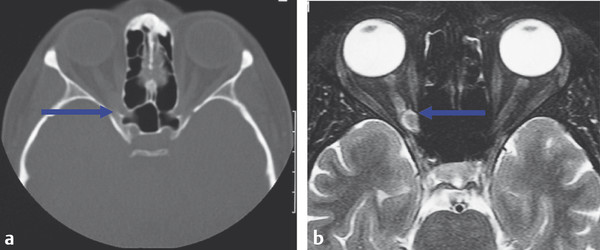

Extraocular muscle enlargement, for example, suggests a number of potential differential diagnoses:

Thyroid orbitopathy (Fig. 18‑15a,b).

Myositis (Fig. 18‑15c,d).

Metastases (Fig. 18‑15e,f).

Lymphoma.

Arteriovenous shunts.

Amyloidosis.

Chronic lymphatic leukemia.